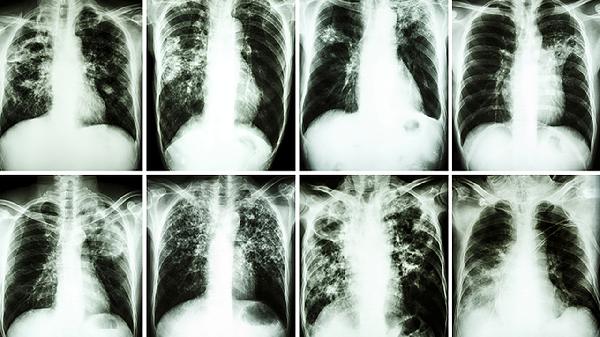

免疫调节剂通过激活机体免疫系统抗肿瘤,包括PD-1抑制剂帕博利珠单抗注射液、CTLA-4抑制剂伊匹木单抗注射液等。这类药物可能引发免疫相关不良反应如肺炎、结肠炎等,需密切监测并及时处理免疫毒性。治疗前需评估患者自身免疫性疾病史和感染风险。